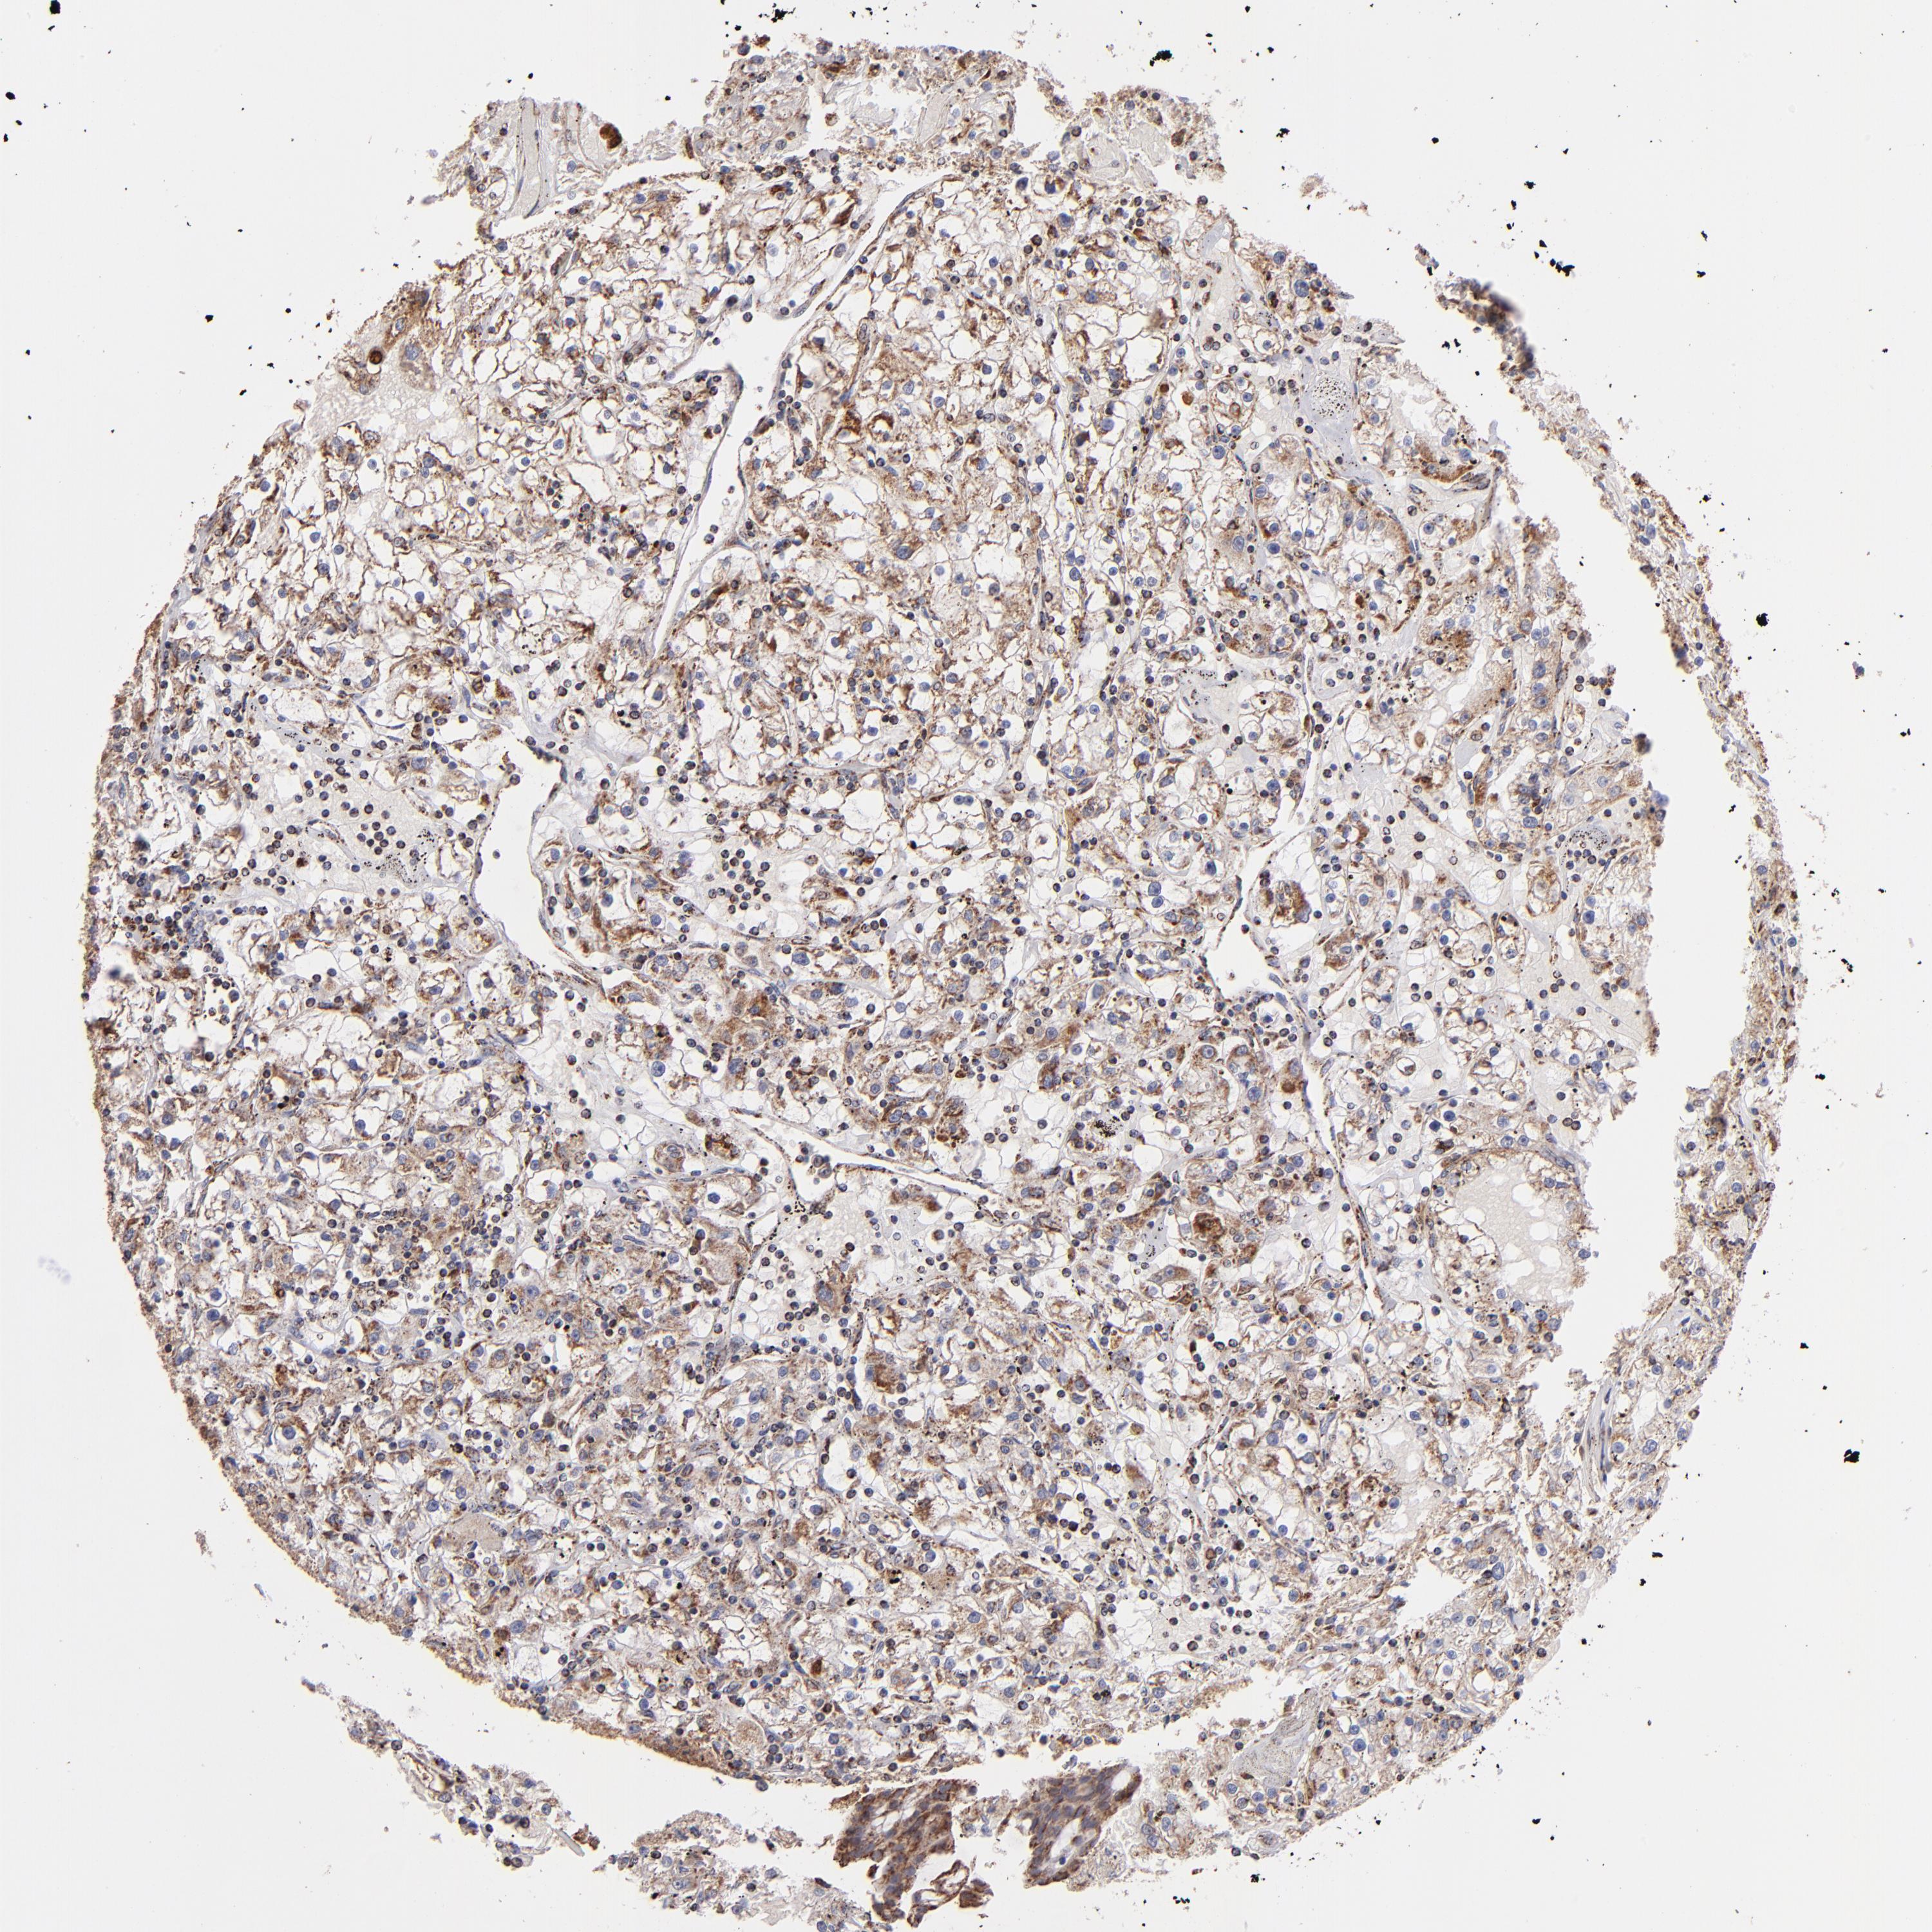

KIDNEY RENAL CLEAR CELL CARCINOMA (VALIDATION) - Interactive survival scatter ploti

The Survival Scatter plot shows the clinical status (i.e. dead or alive) for all individuals in the patient cohort, based on the same data that underlies the corresponding Kaplan-Meier plots. Patients that are alive at last time for follow-up are shown in blue and patients who have died during the study are shown in red.

The x-axis shows the expression levels (FPKM) of the investigated gene in the tumor tissue at the time of diagnosis. The y-axis shows the follow-up time after diagnosis (years). Both axes are complimented with kernel density curves demonstrating the data density over the axes. The top density plot shows the expression levels (FPKM) distribution among dead (red) and alive patients (blue). The right density plot shows the data density of the survived years of dead patients with high and low expression levels respectively, stratified using the cutoff indicated by the vertical dashed line through the Survival Scatter plot. This cutoff is automatically defined based on the FPKM cutoff that minimizes the p-score. The cutoff can be changed by dragging the vertical line or by entering a cutoff value in the square labeled "Current cut-off".

Under the Survival Scatter plot the p-score landscape (black curve; left axis) is shown together with dead median separation (red curve; right axis). Dead median separation is the difference in median mRNA expression between patients who have died with high and low expression, respectively. It is calculated as follows: median FPKM expression of dead patients with high expression - median FPKM expression of dead patients with low expression. This is intended to aid the user in visually exploring custom cutoffs and the associated p-scores and dead median separation.

Individual patient data is displayed and can be filtered by clicking on one or more of the category buttons on the top of the page. Categories describing expression level and patient information include: high, low, alive, dead, female, male and tumor stages. The scale of the x-axis can be toggled between linear and log-scale by clicking on the "x log" button. Mouse-over function shows TCGA ID, patient information and mRNA expression (FPKM) for each patient.

& Survival analysisi

Kaplan-Meier plots summarize results from analysis of correlation between mRNA expression level and patient survival. Patients were divided based on level of expression into one of the two groups "low" (under cut off) or "high" (over cut off). X-axis shows time for survival (years) and y-axis shows the probability of survival, where 1.0 corresponds to 100 percent.

DLST is not prognostic in Kidney Renal Clear Cell Carcinoma (validation)

: 57.84

Average pTPM 52.7

Number of samples 100